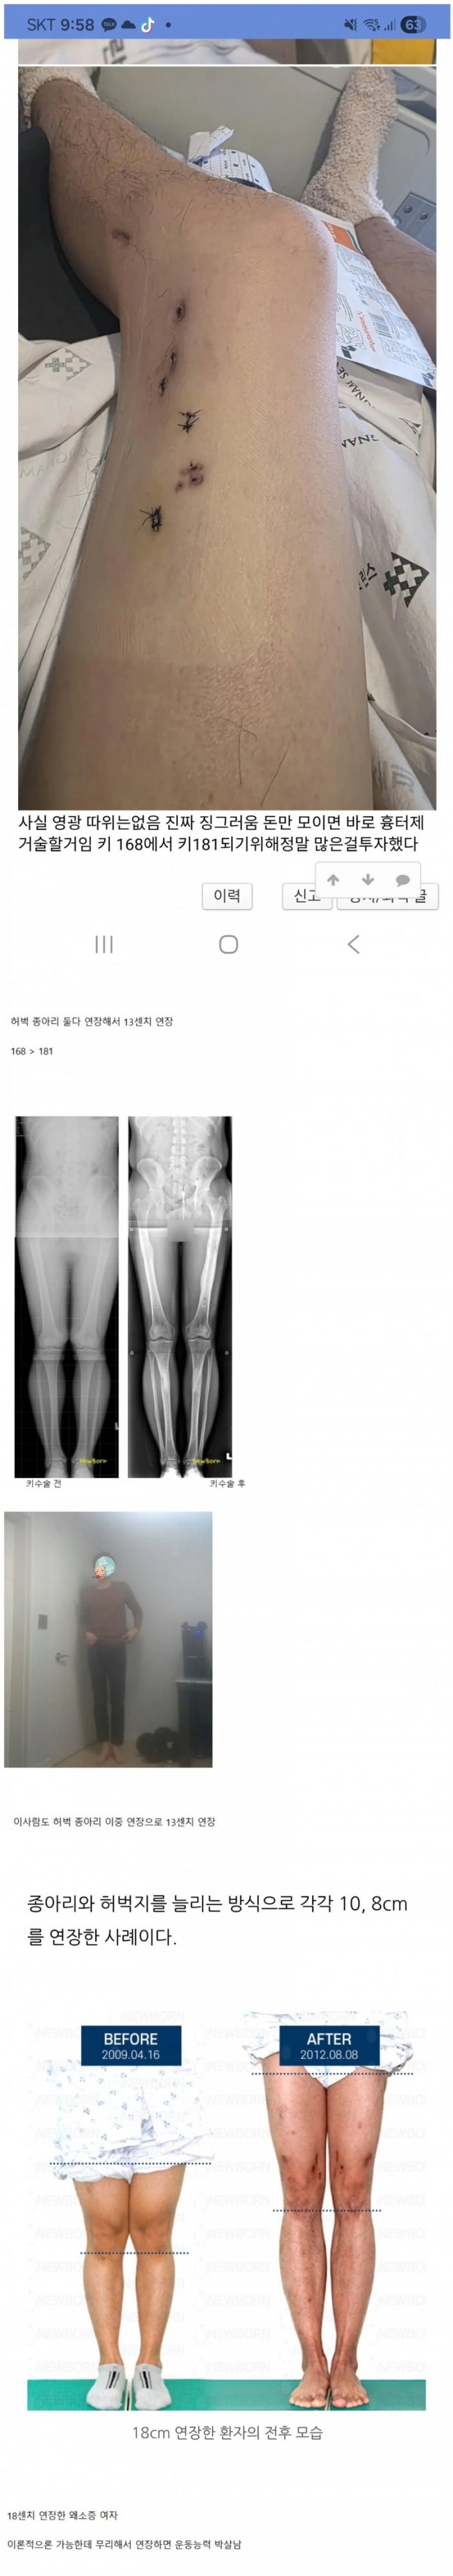

키 13센치 연장한 사람